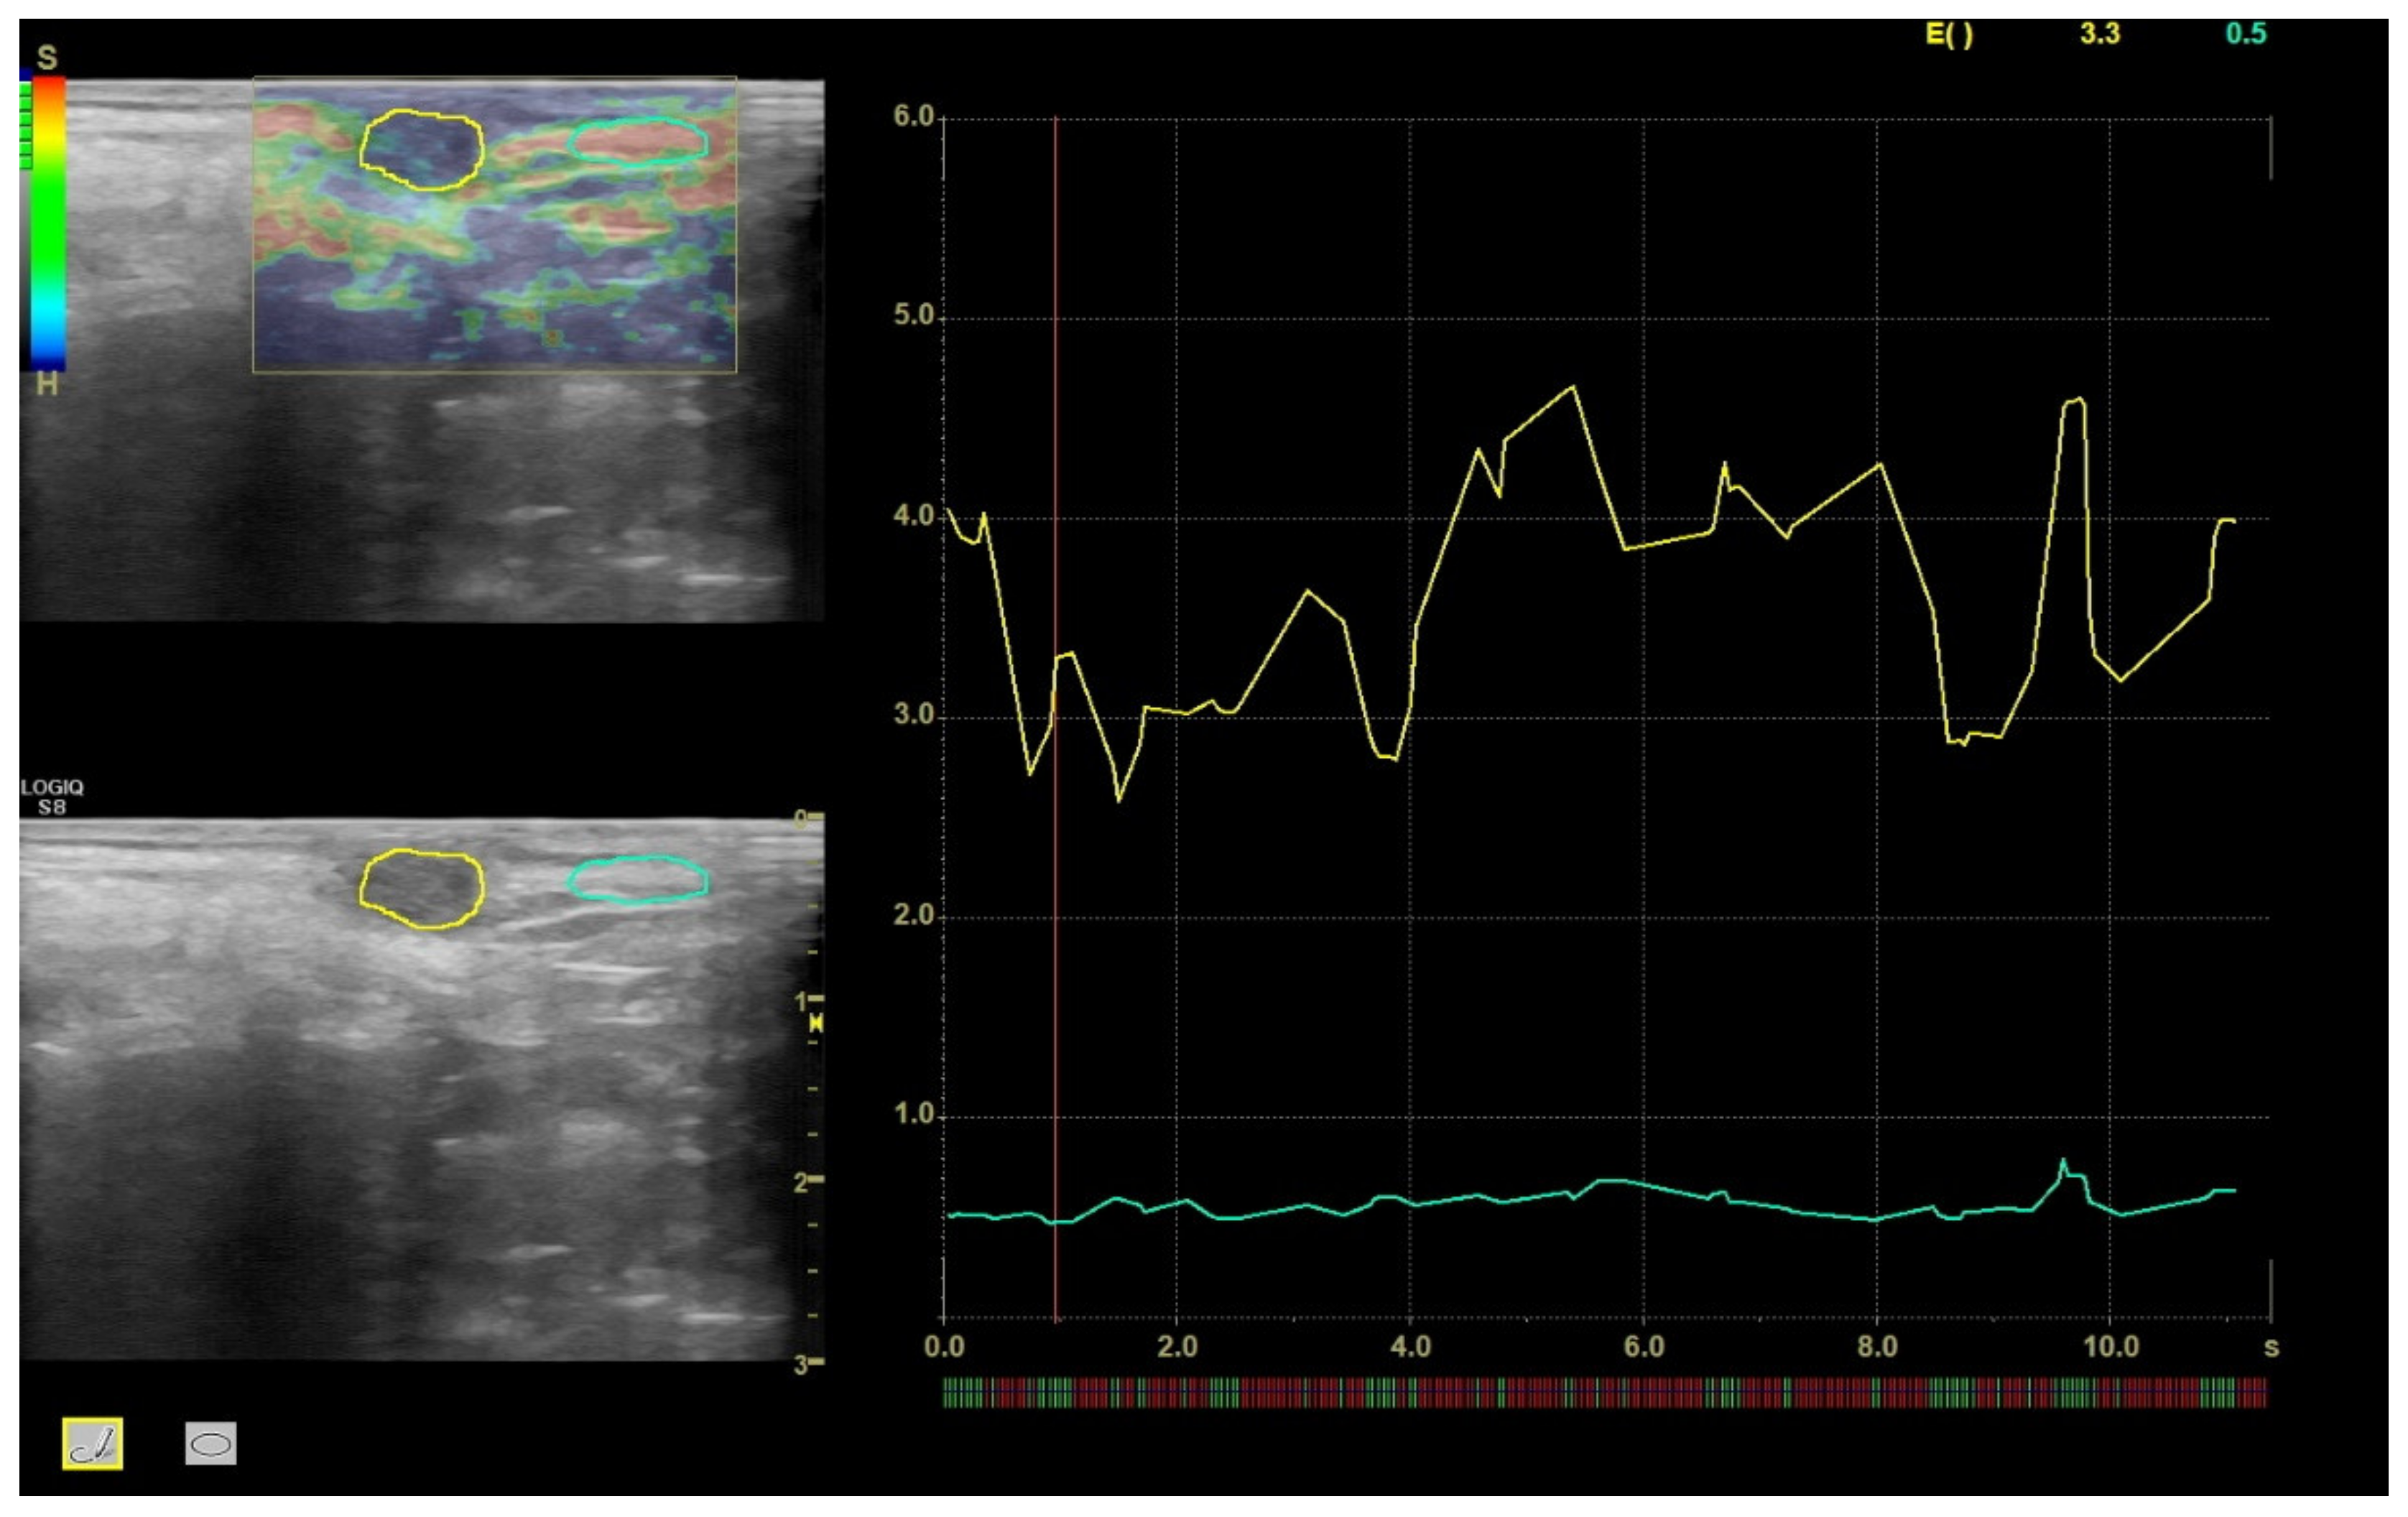

2.2. Ultrasound Sonoelastography

3.1. Sonoelastography and Correlation between Elastographic Parameters